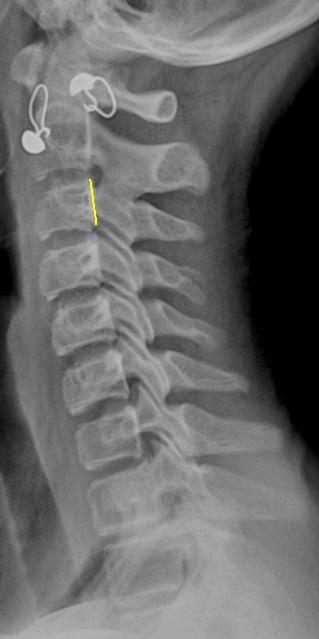

Речь идет не о "подвижности в суставе", а о нестабильности в сегменте. Задний контур С3 помечен "желтым". Обратите внимание, как смещаются позвонки в положении сгибания и разгибания с учетом "заднего контура".